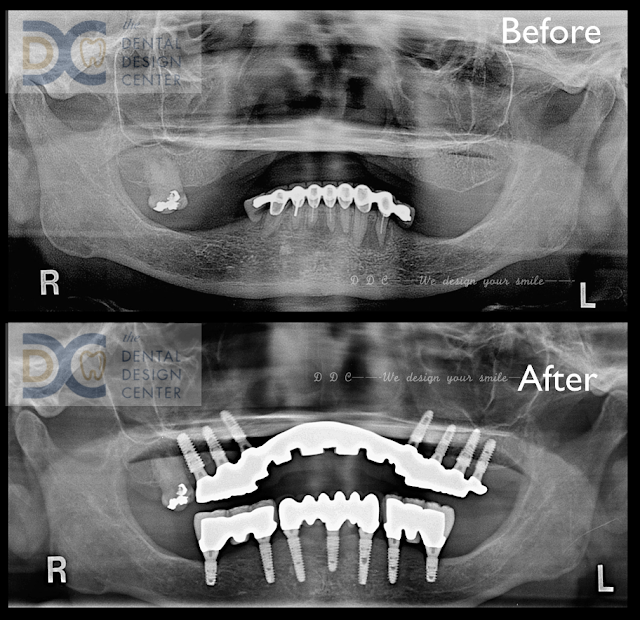

Full mouth implants in severe maxillary resorbed ridge.

Initial OPG x-ray and intra-oral picture show a failed mandibular natural teeth bridge.

Due to the severely resorbed ridge, implants were placed in the posterior maxilla.